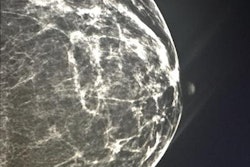

Breast cancer is a leading cause of death in women and is the most common cancer in the U.K., with 42,000 new cases diagnosed in England in 2012, the most recent year for which figures are available. The establishment of a national breast screening program in the U.K. has led to a significant rise in both the number of breast cancer cases and in the complexity of diagnostic breast imaging.

The situation could worsen if proposals to expand mammography screening to a broader age range of women are adopted. Currently, only women ages 50 to 70 are covered by the program, but clinical trials are currently underway to determine whether this range should be expanded to women ages 47 to 73. This would increase the number of women covered by the program by 28%, from 8 million to 10.2 million, the report notes.